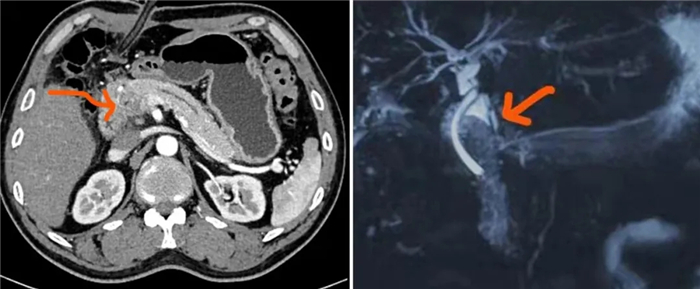

近期,西藏大學(xué)附屬阜康醫(yī)院普外科收治了2名患者,在各科室的共同努力下為患者實(shí)施了“胰十二指腸切除術(shù)”,并將胰腸吻合術(shù)的術(shù)式進(jìn)行了技術(shù)革新,降低了手術(shù)并發(fā)癥帶來的風(fēng)險,為患者健康、安全康復(fù)奠定了堅實(shí)的基礎(chǔ)。

胰十二指腸切除術(shù)是外科手術(shù)中的一項高要求且復(fù)雜的手術(shù),在胰十二指腸切除手術(shù)過程中,需將胰頭、十二指腸和膽總管進(jìn)行切除并重建,這樣的手術(shù)對外科醫(yī)生來說最具挑戰(zhàn)性。而胰瘺一直都是術(shù)后最常見、最嚴(yán)重的并發(fā)癥,其危害性主要在于被膽腸液激活的胰液漏入腹腔,腐蝕周圍組織,非常容易引起致命性大出血或不易控制的感染,造成患者死亡。

為了降低并發(fā)癥帶來的嚴(yán)重后果,西藏大學(xué)附屬阜康醫(yī)院普外科通過不斷探索,改良并創(chuàng)新了胰腸吻合術(shù)的術(shù)式,在防止胰瘺方面初步顯現(xiàn)了其優(yōu)勢,使患者在很大程度上獲益。

目前,該項術(shù)式已在手術(shù)中得到應(yīng)用,術(shù)后患者均未發(fā)生胰瘺現(xiàn)象,并且在多次回訪的過程中,患者的各項指標(biāo)都在正常范圍內(nèi)。